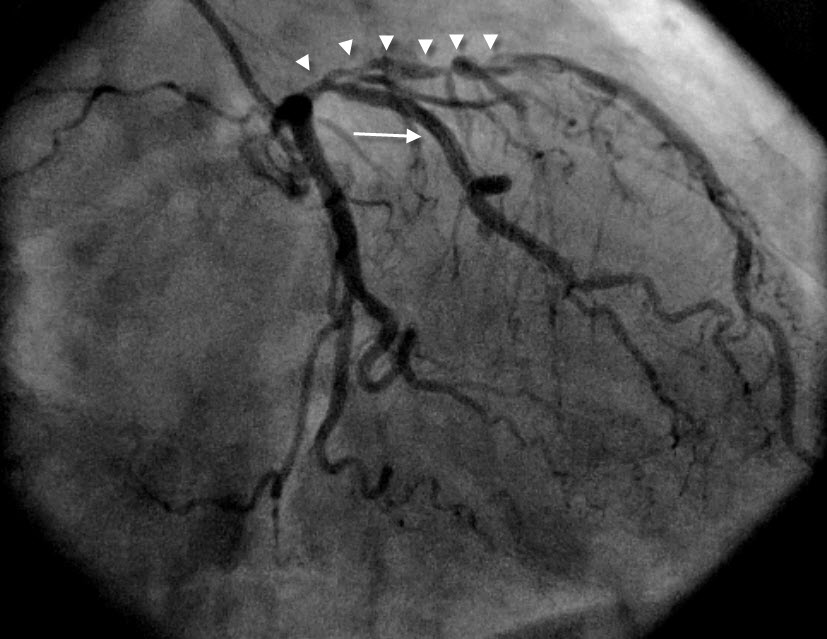

We present herein the case of a woman suffering from acute inferior myocardial infarction referred to our hospital for emergency catheterization after failed fibrinolysis and treated successfully with transradial rescue PCI. The case presentation is followed by a concise overview of data supporting the wider use of the radial approach, especially focusing on acute coronary syndromes.